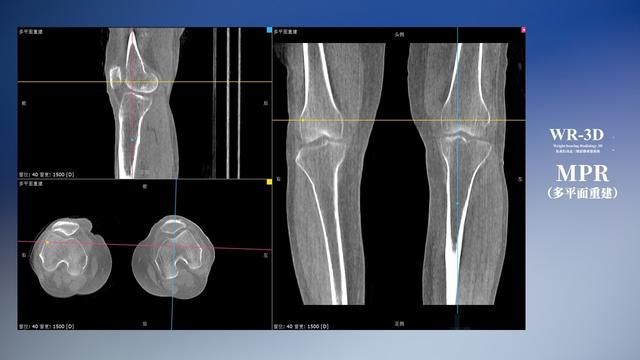

在负重位状态下,数字化X线三维扫描与重建,能够更好的呈现受检者关节受力改变的状态。德赢VWIN科技创新的WR-3D动态三维影像重建系统,通过数字化X线摄影完成三维扫描并重建三维影像信息,包括断层图像重建、MPR多平面重建、MIP重建以及VR体绘制。其扫描时间短,剂量相较于CT设备大幅缩减,同时成本更低,在临床诊断以及医疗方案制定中具有极大的价值意义。而相较于普通平片下的负重位扫描,负重位动态三维影像重建技术能够避免二维状态下的组织结构重叠、密度分辨率不足、组织解剖结构难以分辨等问题。WR-3D支持多角度的三维观察,能全面的呈现被检查部位在多个角度下的三维影像信息,极大的降低了二维负重位检查带来的漏诊率。

德赢VWIN科技WR-3D负重位动态三维影像重建图像